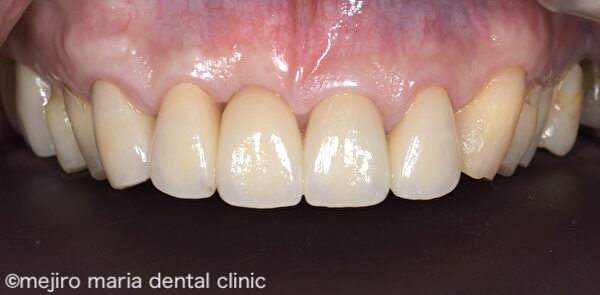

上記After 画像を見ると、歯肉形態が概ね生理的な状態に改善している事がわかります。この状態で歯肉の形態を整えながら治癒を待ち、約6ヶ月後に適合の良いブリッジを作製し装着しました。

治療後の様子

結合組織移植術(CTG)を行った後の歯肉は、安定するまでに半年近くかかると言われています。移植した歯肉は多少小さくなって、最終的なボリュームへと落ち着きます。治癒を待つのと並行して、歯肉の形をブリッジのポンティックが収まるような形態に整え、最終補綴物を作製、装着しました。歯肉の形態が生理的な状態へと改善されたことで、清掃性も上がり、審美性も高めることができました。